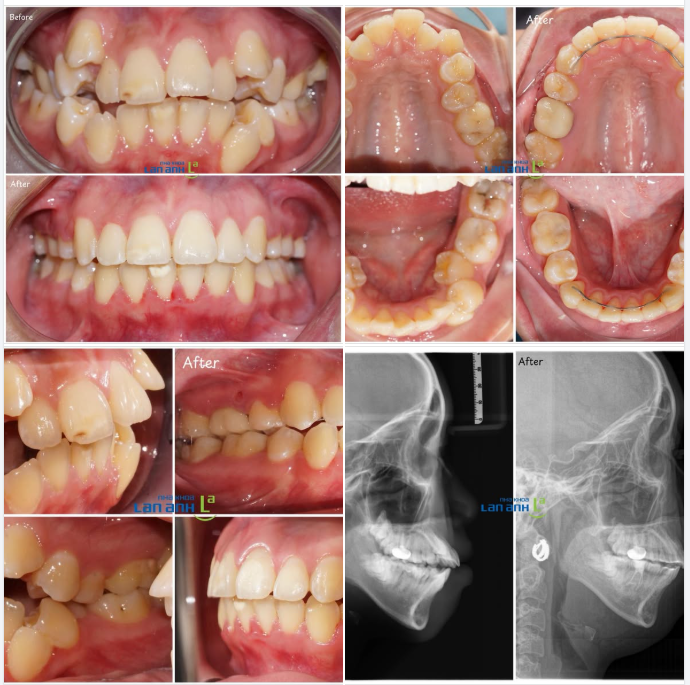

P/s: Hình ảnh một ca niềng răng mắc cài trong 2.5 năm.